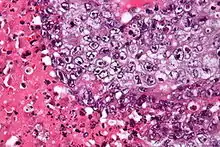

| Micrograph of an embryonal carcinoma showing its typical features – prominent nucleoli, marked nuclear atypia, necrosis, and nuclear overlap. H&E stain. | |

The gross examination usually shows a two to three centimetre pale grey, poorly defined tumour with associated haemorrhage and necrosis.[2]

The microscopic features include: indistinct cell borders, mitoses, a variable architecture (tubulopapillary, glandular, solid, embryoid bodies – ball of cells surrounded by empty space on three sides), nuclear overlap, and necrosis.